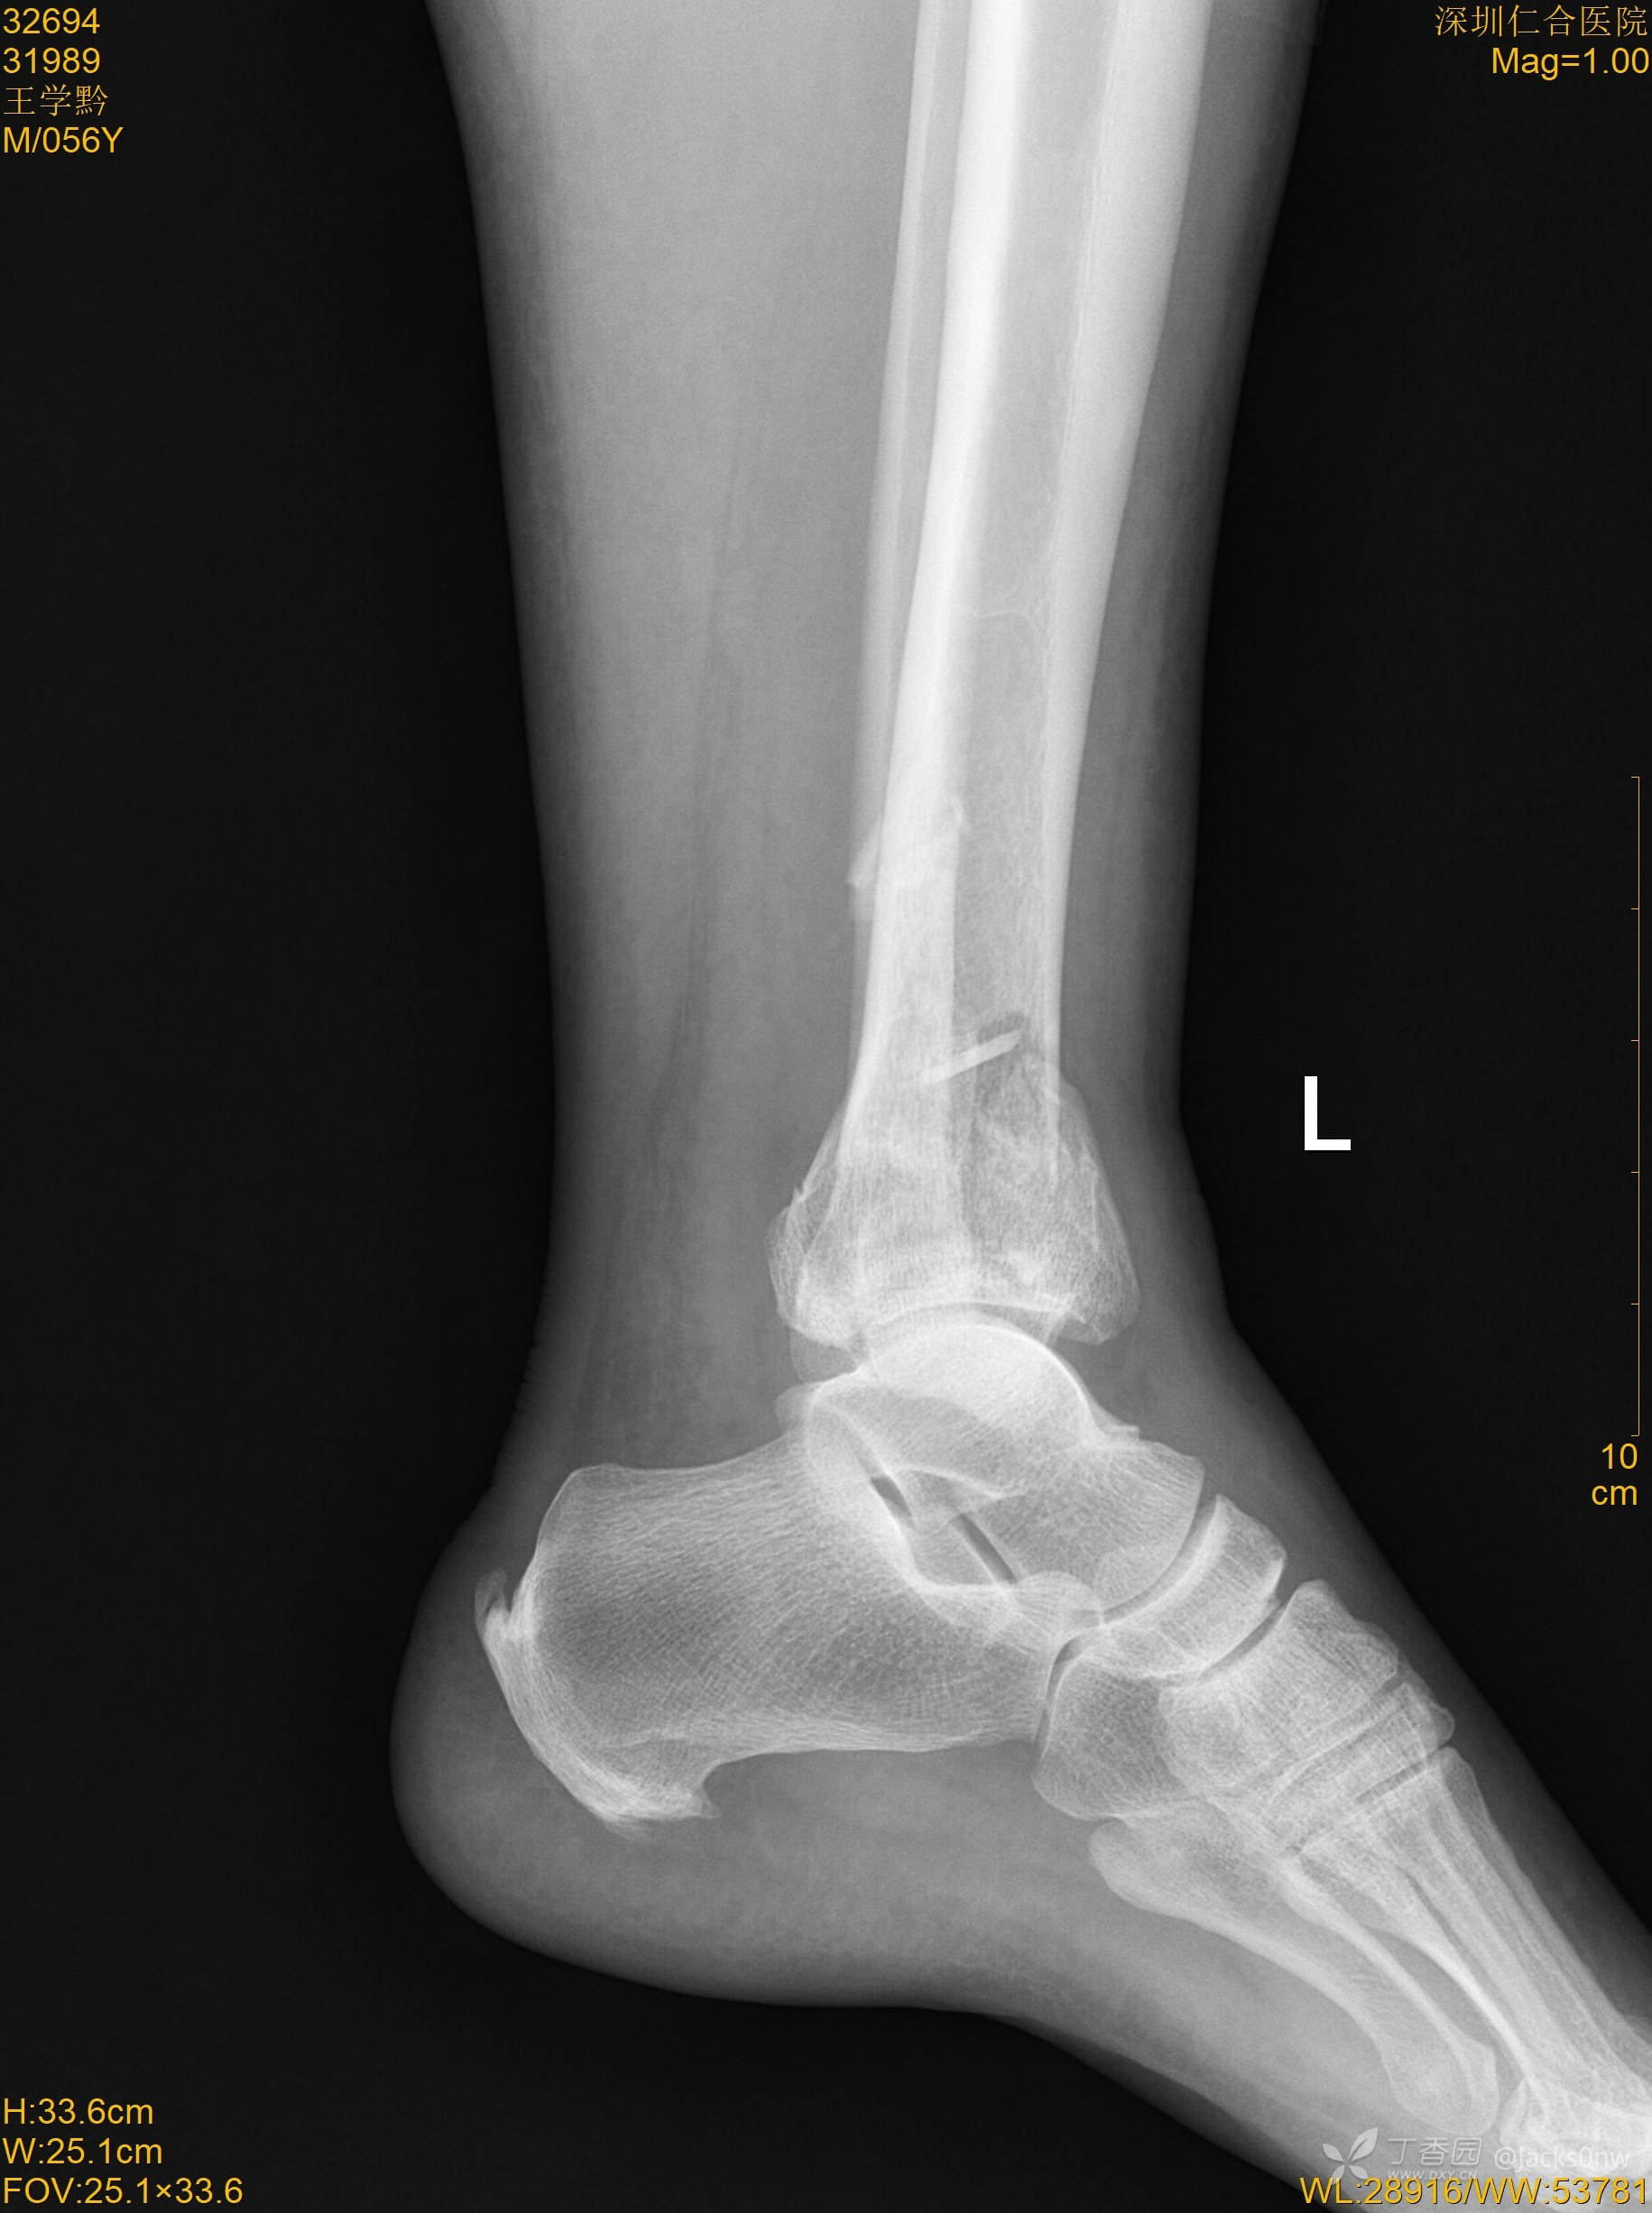

辅助检查:2022.10.26,DR左踝部:Pilon骨折。

术前